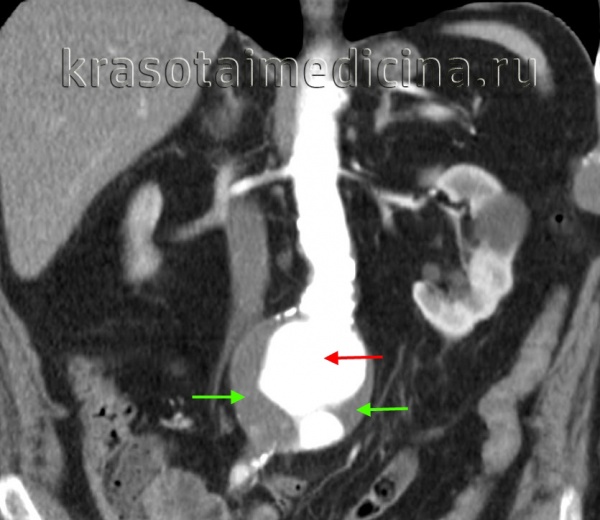

КТ-ангиография аорты. Аневризма брюшной аорты над бифуркацией. Просвет аневризмы (красная стрелка), пристеночный тромб (зеленая стрелка).